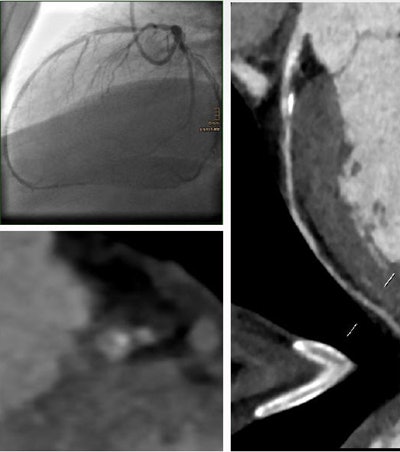

A total of 80 patients (mean age 64.9 years) with 101 lesions in the proximal segments underwent either 128-detector-row (73 patients) or 64-detector-row CCTA (7 patients), followed by invasive coronary angiography. The MLA was quantified by CT along with minimum lumen diameter, maximal area stenosis, and maximal diameter stenosis.

Results were evaluated for hemodynamic relevance in ICA (defined as fractional flow reserve less than 0.8 or stenosis 70% or greater) and followed by percutaneous intervention or coronary bypass grafting. Receiver operating characteristic (ROC) analysis with stepwise testing (0.1 mm2 MLA increments) also was performed.

According to the results, the optimal cutoff minimal lumen area was 1.8 mm2 or less to predict a positive invasive angiography result (above), This cutoff point yielded a sensitivity of 92.11% (78.6% to 98.3%), a specificity of 87.30% (76.5% to 94.4%), and an area under the curve (AUC) of 0.95 (0.91 to 0.99) for predicting stenosis significance at CCTA, Plank said.